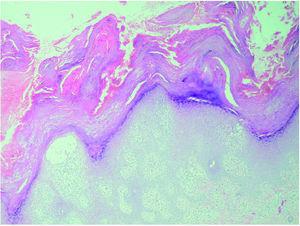

Se realizaron dos biopsias cutáneas; una de dorso de dedo de la mano (fig. 3), que mostró una prominente hiperqueratosis y acantosis, con focos de paraqueratosis e hipogranulosis, algunas áreas de exocitosis y espongiosis, queratinocitos necróticos e infiltrado linfocítico perivascular. La segunda fue tomada de una lesión ampollosa localizada en la superficie de una placa eritematoedematosa del dorso de la rodilla. Su estudio histopatológico (fig. 4) mostraba un despegamiento subepidérmico con un infiltrado inflamatorio superficial de linfocitos, neutrófilos y eosinófilos, así como dermatitis de interfase con degeneración vacuolar de la capa basal. La inmunofluorescencia directa (IFD) de la piel perilesional de la segunda biopsia demostró la existencia de depósitos granulares de inmunoglobulinas (IgM, IgA) y C3 en la membrana basal (fig. 5).

Fig. 3.--Hiperqueratosis paraqueratósica con acantosis, focos espongióticos e infiltrado inflamatorio perivascular. (Hematoxilina-eosina, ×40.)